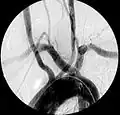

Angiografía mostrando arteria subclavia aberrante derecha